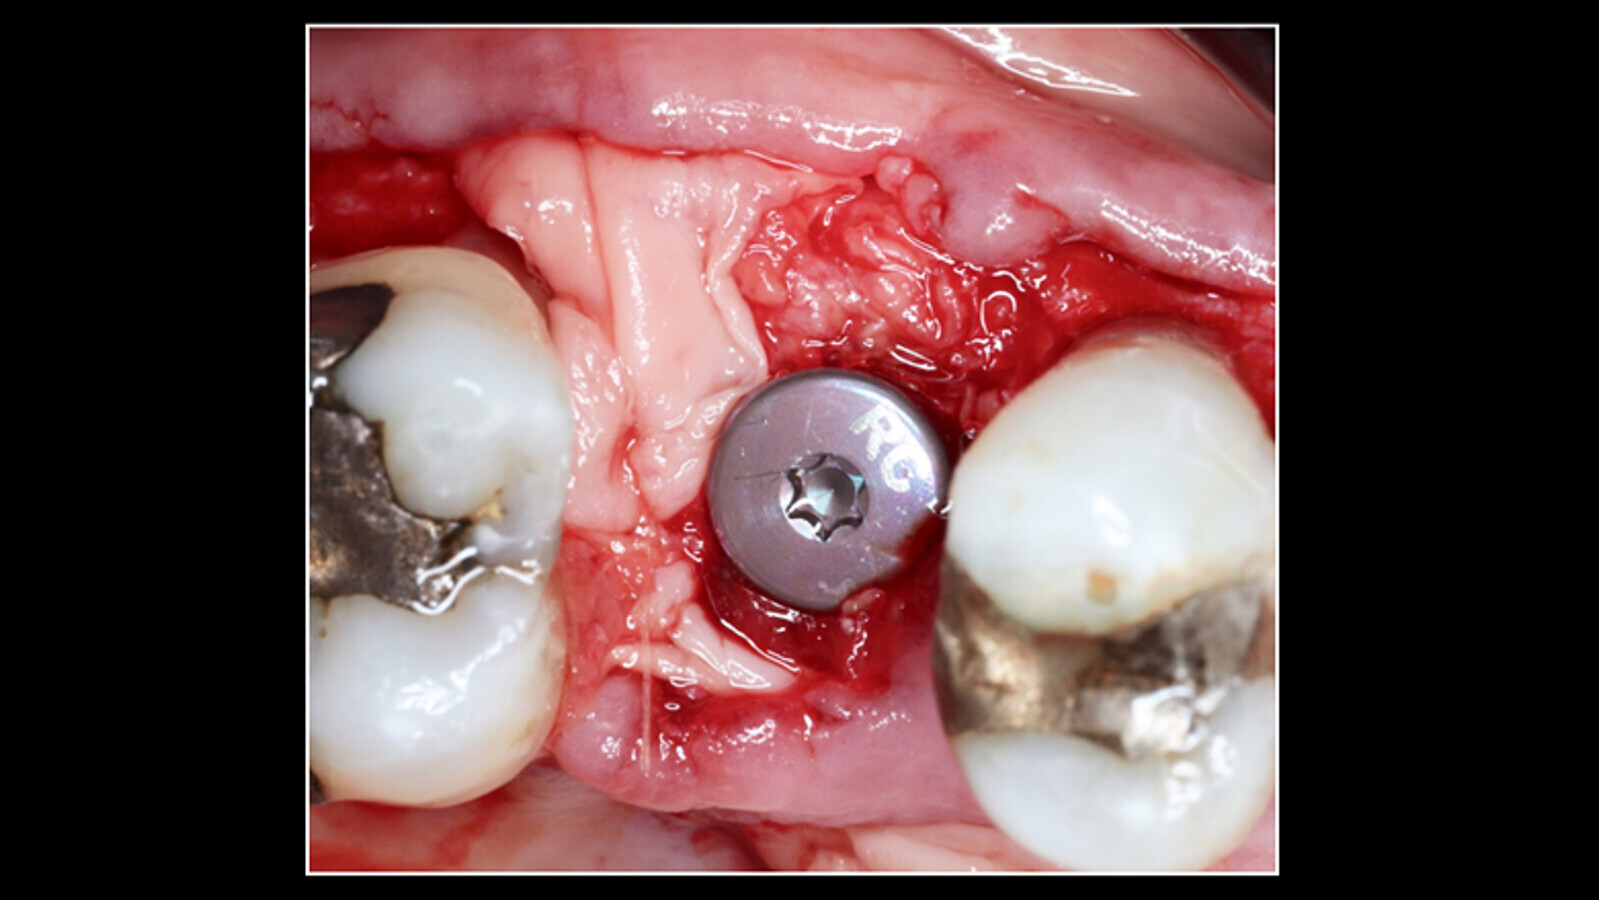

Figura 1. El examen clínico muestra enrojecimiento de la zona, presencia de sangrado, profundidad al sondaje vestibular de 8-8-8 mm y distal 8-8-8 mm. (Fotos: Samia Isaac / Ivan Herrera )

Paciente femenino de 67 años de edad, sana, no medicada. Acude a consulta por dolor en zona de segundo premolar superior derecho tratado con implante post-exodoncia, 2 años de evolución; al examen clínico se observa edema, enrojecimiento de la zona, presencia de sangrado (Figura 1), profundidad al sondaje vestibular de 8-8-8 mm y distal 8-8-8 mm.